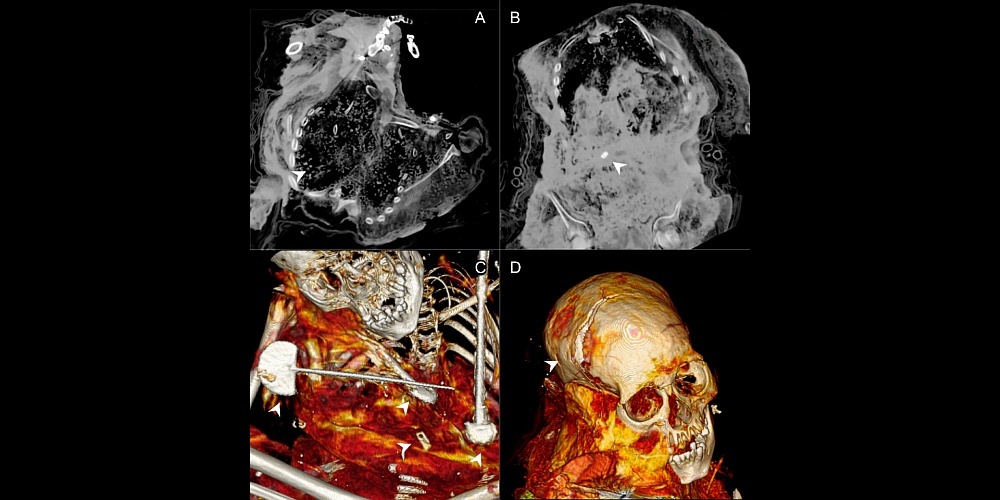

КТ детских останков с вулкана Сара-Сара. / Фото: Journal of Archaeological Science: Reports

Ранее ученые предполагали, что для капакочи использовали только здоровых детей и подростков. Но это исследование показало, что это было не всегда: у некоторых жертв были заболевания. Так у одного погибшего ребенка исследователи выявили патологию пищевода и кальцинаты в легких.

Исследование останков другого ребенка показало, что вскоре после смерти с телом проводились определенные манипуляции. Ученые установили, что многие кости внутри были смещены, а некоторые даже отсутствовали. Кроме того, внутри грудной клетки были обнаружены инородные предметы, такие как камни и куски ткани. Вероятно, труп пытались привести в порядок, поскольку сохранность тела была важным элементом ритуала. Это первый случай подобной намеренной мумификации.